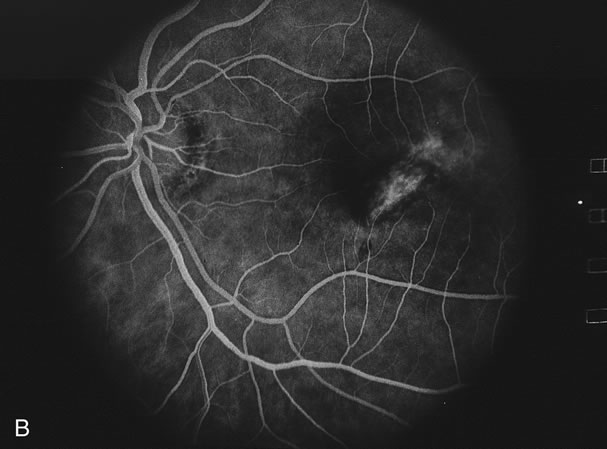

Fig. 16. A. Color fundus photograph showing the jigsaw pattern of choroidal and retinal atrophy extending from the disc along the arcades. At the inferior edge of the superotemporal lesion there is a recurrence noted by the grayness of the retina. B. Fluorescein angiogram in the laminar venous phase showing a large window defect in the area of inactive choroiditis and blockage of the choroidal fluorescence in the area of active choroiditis. C. In the late phase of the fluorescein angiogram there is staining of the edges of the inactive choroiditis and marked hyperfluorescence in the area of active choroiditis.

Fig. 17. A. Classic inactive case of serpiginous choroiditis showing the jigsaw pattern of disease surrounding the fovea. B. Fluorescein angiogram showing staining of the edges of the inactive serpiginous choroiditis. There is blocked fluorescence in the areas of hyperplasia of the retinal pigment epithelium. C. Indocyanine green angiogram showing absence of fluorescence in the area of inactive choroiditis.